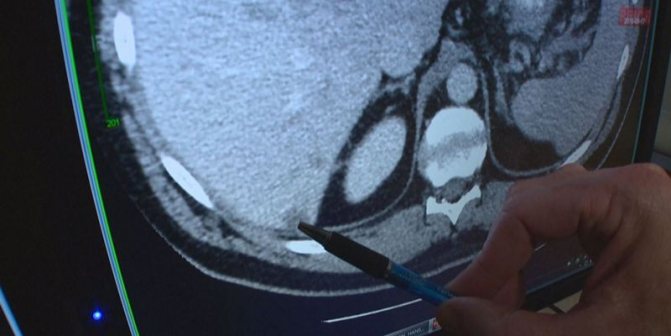

- КТ с контрастом;

- КТ (компьютерная томография). С помощью этого метода изучается поджелудочная железа в любой из ее частей, причем становится возможным выявление даже незначительной по размерам опухоли, которую не определяет УЗИ. Далее, при наличии опухолевого образования, определяется, из каких конкретно клеток оно состоит – применяется для этого следующее в нашем списке исследование.